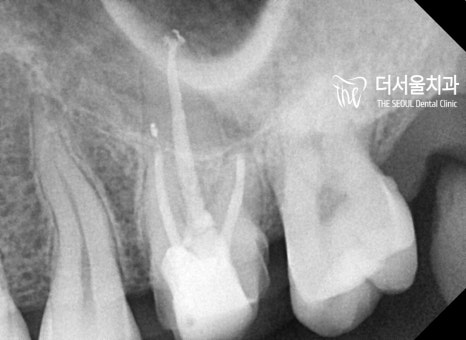

뿌리 끝까지 근관충전을 마치고

코어 작업을 진행했습니다.

이제 자연치와 유사한 형태로

크라운을 만들어주면 모든 과정이 끝나게 되는데요.

자, 최종 보철까지 완성된 모습을

한번 확인해볼까요?

PFM으로 만들어진 구치부 보철입니다.

지르코니아가 아님에도 불구하고

심미성이 떨어지지 않네요.

구치부는 ‘잘’만 만든다면

PFM도 좋은 선택이 될 수 있습니다ㅎㅎ